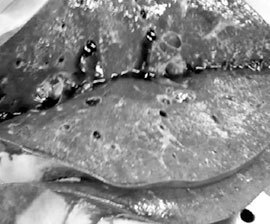

Желудочковый индекс = 0,7 ЛЖ = 140 г, ПЖ = 100 г

Легочное сердце ЛЖ = 20 мм, ПЖ = 10 мм

Рис. 5. Легочное сердце